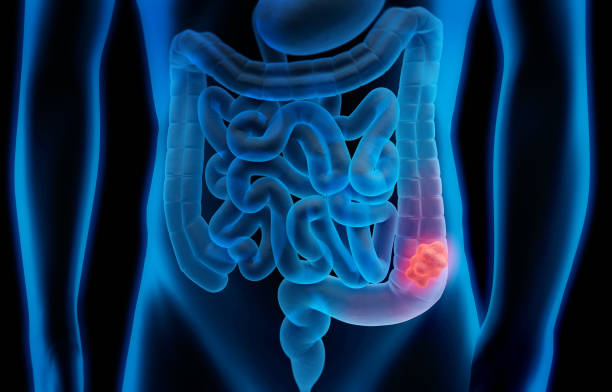

직장암은 대장 내의 직장 부분에서 발생하는 악성 종양을 말합니다. 직장은 대장의 하부 1/3 부분으로 대장 내에서 최종 소화물을 보관하고 직장 벽에는 점막, 근층, 섬유층, 근막층으로 구성되어 있습니다. 직장암은 초기에는 대부분 증상이 없기 때문에 발견이 어려울 수 있으며, 늦게 발견되면 치료하기 어려울 수 있습니다. 따라서 주기적인 검진과 조기 발견이 중요합니다.